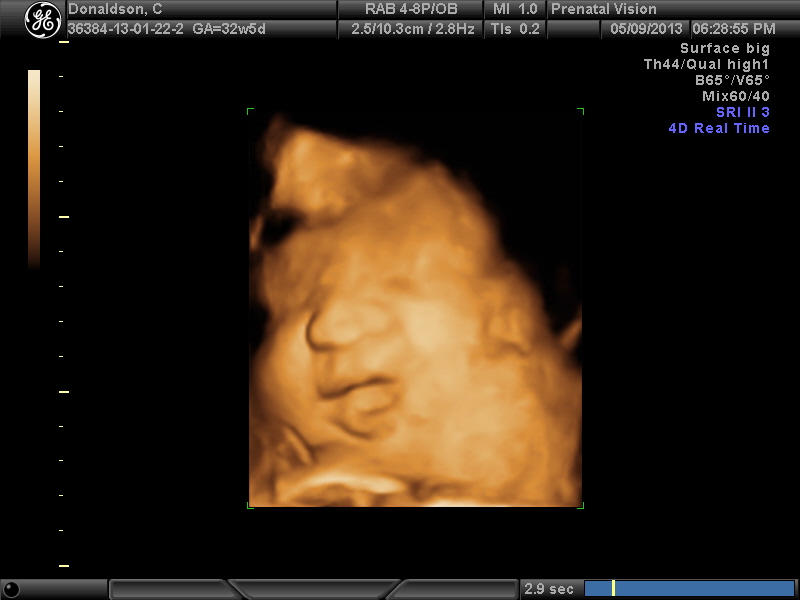

IMAGES_17 May 13, 2013 by Courtney Leave a comment ← Previous Image Next Image → 32w5d Like Loading...